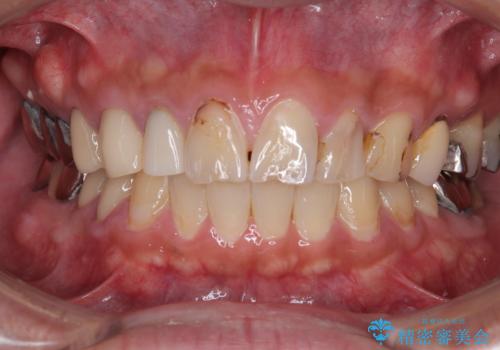

- 患者様は「前歯の見た目をきれいにしたい」というご希望で来院されました。

拝見すると、上顎前歯部にはCR充填(レジン修復)が繰り返し行われており、つぎはぎ状になっていました。そのため、

色調が不自然

形態にばらつきがある

笑ったときに治療跡が目立つ

といった審美的なお悩みが認められました。

また、右上側切歯は根管治療が必要な状態でした。